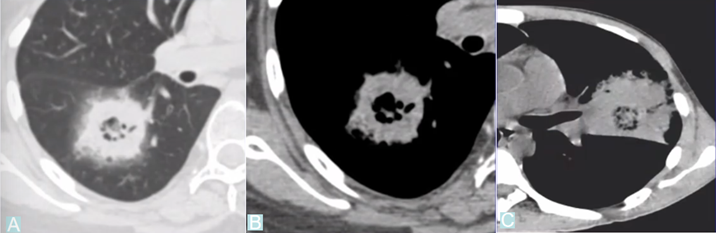

下图为一肿块,周围有晕征,中间有小气泡,增强扫描可见大片坏死,没有强化(图19),这种特征非常像曲霉感染,但最终穿刺病理证实为毛霉感染。其破坏范围更广。临床上,在诊断不清的情况下,一定要做增强扫描,能够帮助确定组织强化的程度。患者出现了胸腔积液,其中的小气泡更大,这是毛霉的特征。

图片

图19  毛霉感染

曲霉的破坏程度与曲霉菌丝生长相对成比例,其破坏范围形成的坏死、空洞及分隔均少于毛霉,而毛霉的破坏力更强。下图是一个结节,周边有晕征,说明病变是血管侵袭性,其中有很多小气泡,没有液平面,说明有菌丝的存在,菌丝固定了坏死物。但纵隔窗看到分隔特别粗大,小气泡特别大,说明坏死占的比例更多,坏死程度更严重,而菌丝的生长与坏死程度不成比例,所以是“坏死多菌丝少”,这是毛霉的特征。而曲霉感染则是“坏死多菌丝多”,坏死物相对固定,小气泡并未形成大的空洞。这也是曲霉和毛霉重要的鉴别点(图22)

图22  毛霉和曲霉感染坏死、空洞的区别

注:A、B为毛霉所致病变,空洞内分隔粗大不均,空洞更大;C为曲霉所致坏死物固定,小气泡多。